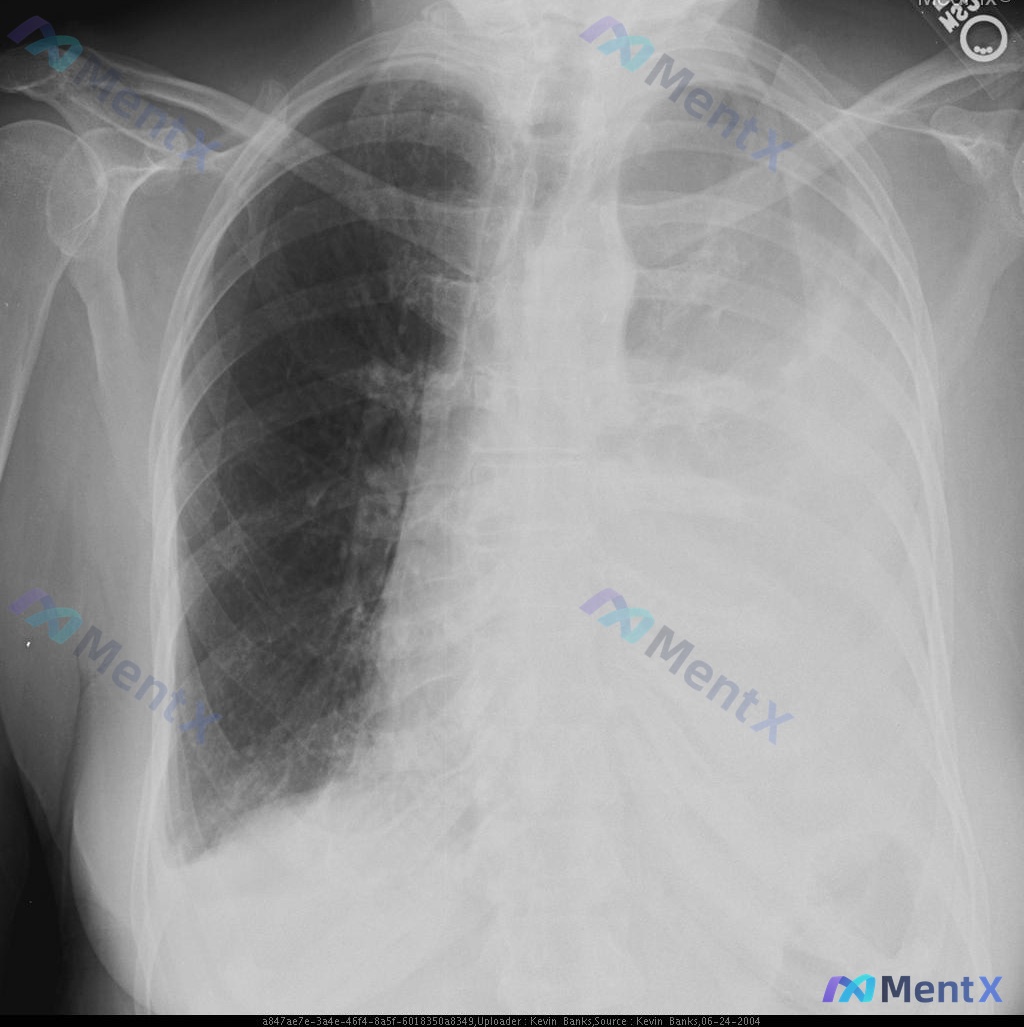

整理了一个比较有警示意义的病例,核心不是选哪种药,而是不要被「药物调整」带偏了节奏。 病例基本情况 70岁女性,养老院居住,因「发热、呼吸急促、咳嗽伴恶臭痰」入院。 - 体征:左侧基底啰音、叩诊浊音 - 初始胸片:左下叶肺炎 - 初始治疗:万古霉素 + 大剂量左氧氟沙星 病情变化与核心检查 但治疗后...